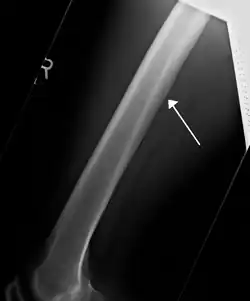

A nutrient artery feeding the femur seen on X-ray

The nutrient artery (arteria nutricia, or central artery), usually accompanied by one or two nutrient veins, enters the bone through the nutrient foramen, runs obliquely through the cortex, sends branches upward and downward to the bone marrow, which ramify in the endosteum–the vascular membrane lining the medullary cavity–and give twigs to the adjoining canals. Nutrient arteries are the most apparent blood vessels of the bones.[1]

All bones possess larger or smaller foramina for the entrance of the nourishing blood-vessels; these are known as the nutrient foramina, and are particularly large in the shafts of the larger long bones, where they lead into a nutrient canal, which extends into the medullary cavity (bone marrow cavity).[2]